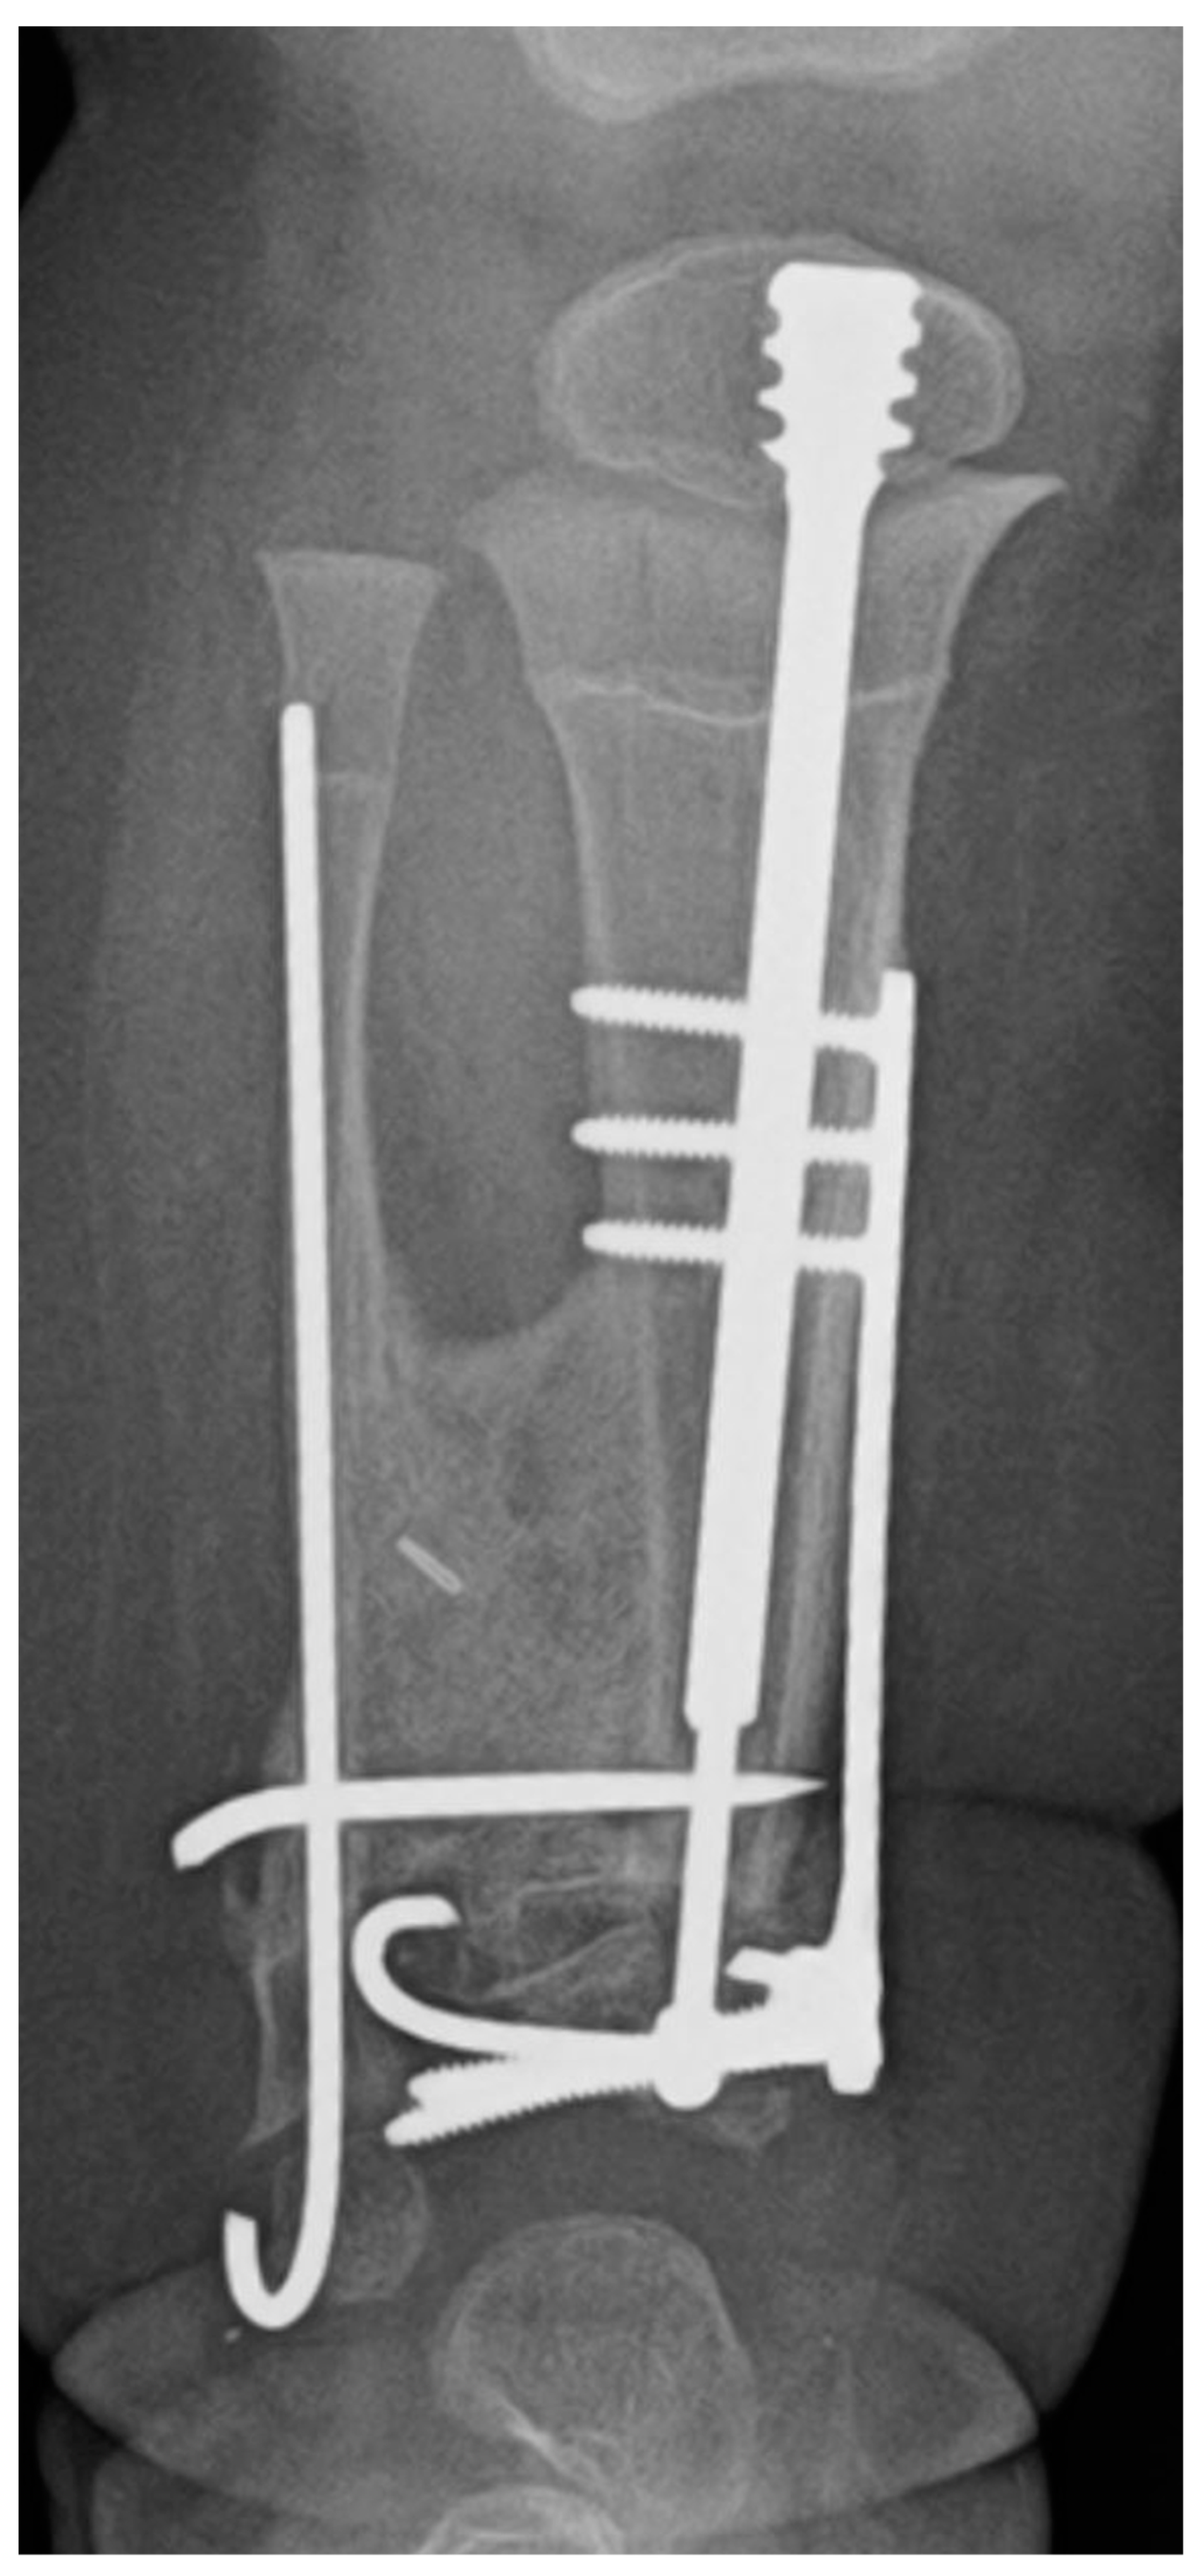

Of the FD rods placed at the time of the index CPT surgery, 26/39 rods (66.7%) were noted to have pulled out of one or more epiphyses. Nine rods migrated across the proximal tibial physis, fifteen rods migrated across the distal tibial physis, and two rods migrated across both physes (Figure 3). Five of twenty-two rods (22.7%) placed at the time of the planned rod exchange also demonstrated migration. Two rods migrated across the distal physis, and three rods migrated across both physes. This did not lead to any additional surgery and was addressed at the time of the planned rod exchange in all cases. Despite rod migration across the physis, no growth arrest was seen in any patient in this study group.

Figure 3. Radiographs demonstrating the various forms of FD rod migration: (a) the rod has pulled out of the distal epiphysis; (b) the rod has pulled out of the proximal epiphysis; (c) the rod has pulled out of both proximal and distal epiphyses. Note the reconstitution of the physis despite the breach by the FD rod.